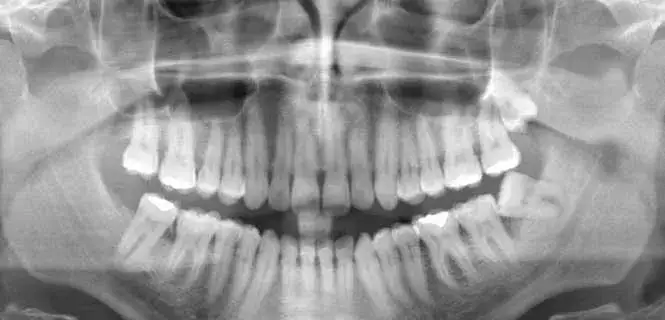

Sprawdź, ile kosztuje zdjęcie panoramiczne zębów w Polsce. Poznaj ceny w różnych miastach i dowiedz się, jakie korzyści niesie to badanie.